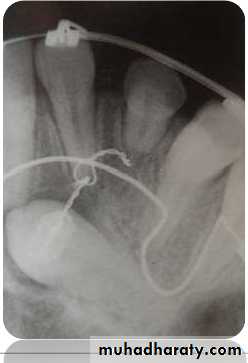

Tube shift technique or Clarke

technique (parallax method)

Principle:

• 2 periapical views of the same object are taken from slightlydifferent angles which can provide depth to the flat 2-D

picture depicted by each of the films individually.• Useful in distinguishing the buccal or lingual displacement of

Mesialangulation

Normal

angulation

Distal

Procedure:

1.In the periapical film, the X-rayis taken in the area of interest

with the X-ray beam passing

perpendicular to a tangent to

the line of arch at this point & at

an appropriate angle to

horizontal plane.

2.In the second film, the X-ray

tube is shifted mesially ordistally round the arch but held

at the same angle to the

horizontal plane. The X-ray

tube should describe between

30-450 of an arc of circle whose

72

Result:

• It is based on the SLOB principle.

• If the object has moved on the same side as thatof the X-ray tube it is lingually placed & if it has

moved on the opposite side it is on the buccalside.

Disadvantage:In cases when canine is highly placed, and

Periapical film shows no superimposition of canine

with the roots of erupted tooth or when

Vertical tube shift method

Left canine is highly placed in OPG. In IOPA left canine moves towards apical 1/3 of lateral

incisor.73